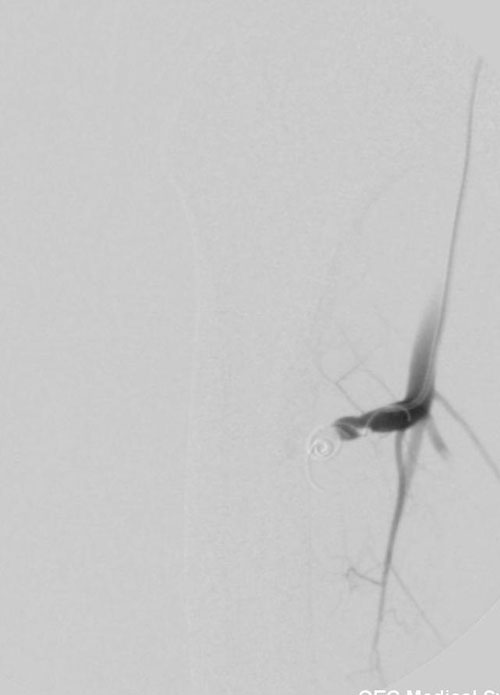

栓塞前造影